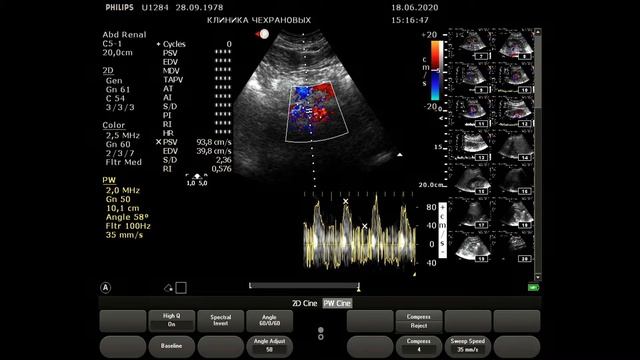

Видео узи артерий

Видео узи артерий 107 фото